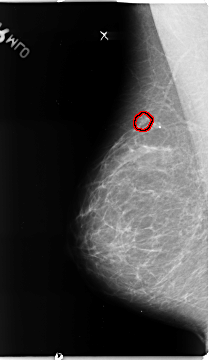

FILE: B_3136_1.RIGHT_MLO.OVERLAY

TOTAL_ABNORMALITIES 1

ABNORMALITY 1

LESION_TYPE CALCIFICATION TYPE PLEOMORPHIC DISTRIBUTION CLUSTERED

ASSESSMENT 4

SUBTLETY 4

PATHOLOGY MALIGNANT

TOTAL_OUTLINES 1

BOUNDARY

RIGHT_MLO LINES 4680 PIXELS_PER_LINE 2712 BITS_PER_PIXEL 12 RESOLUTION 50 OVERLAY